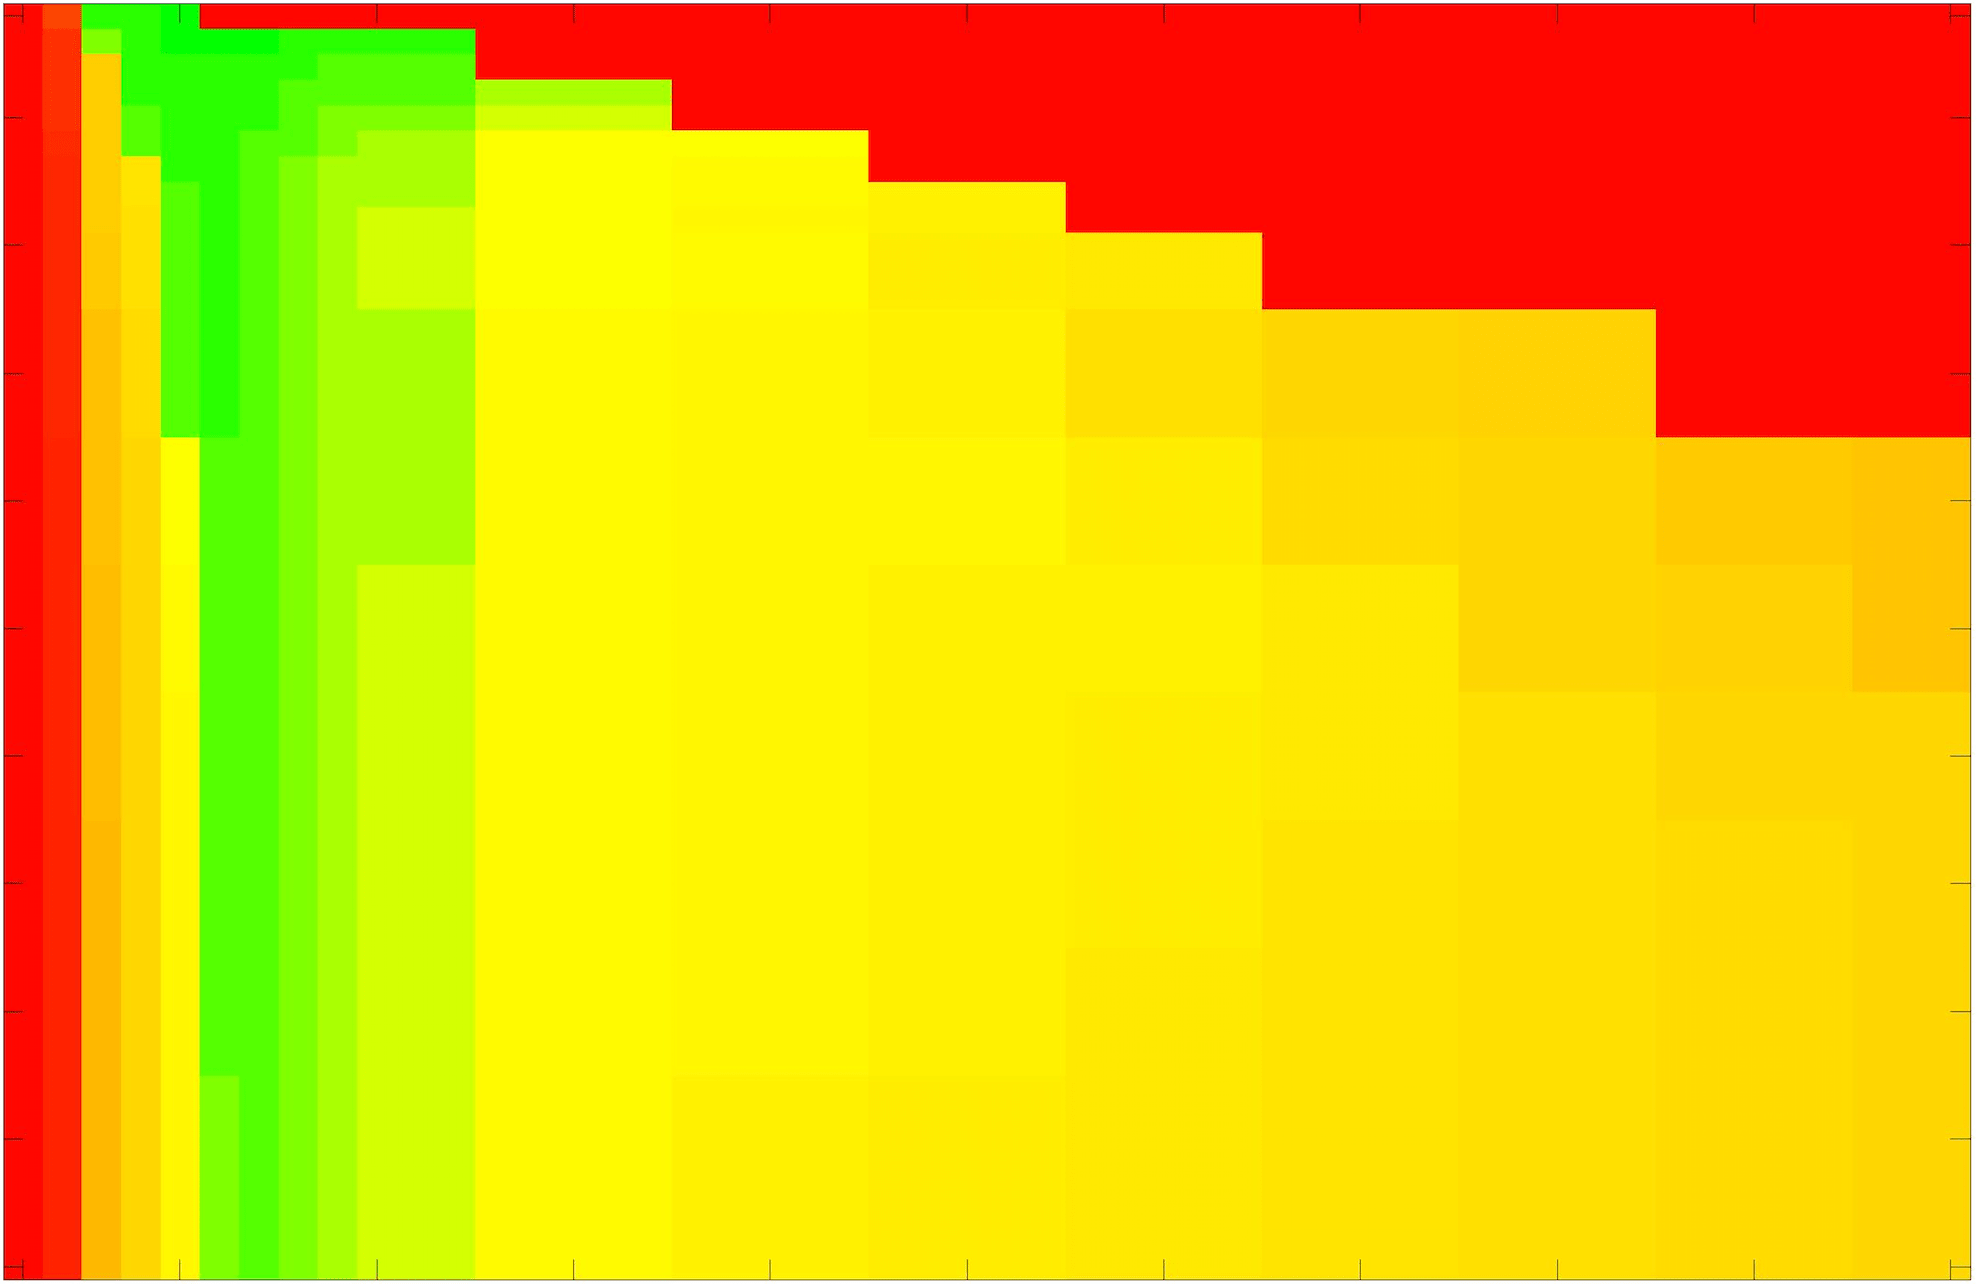

where refers to the number of points in the enclosed region. This takes values in the range , with higher TC values indicating a more accurate segmentation. In the following we will represent accuracy visually from red () to green (), with the intermediate scaling of colours used shown in Fig. 8. This will be particularly relevant in §7.2.

The TC values for the parameter sets are presented as heatmaps in Figs. 11–13. A heatmap is a convenient way to display accuracy results for hundreds of tests concisely. In Fig. 9 we give an example heatmap with the same axes used for those in Figs. 11–13. For each of the combinations of parameter values we give the TC value of the segmentation result and represent it by the appropriate colour. The corresponding colour scale is shown in Fig. 8. Qualitatively, the more green areas of the heatmap the more accurate the model is for a wider set of parameters. Example results for Test Image 5 when varying (with ) for the proposed model are given in Fig. 10. Here it can be seen what each accuracy result corresponds to visually.

Note. The axes have been removed from the heatmaps in Figs. 11–13 for presentational clarity. However, to be explicit, the axes used in all heatmaps are the same as those in Fig. 9.

Synthetic Images. These results are presented in Fig. 11. For Test Images 1–2 we see poor parameter robustness from all competing models, except for GAV which performs reasonably well. However, the proposed model has minimal parameter sensitivity for these images, with good results achieved for almost every combination of values tested. For Test Image 3 all models have a reasonable parameter range (except for RSF), however the proposed model gives better quality results for a wider parameter range. The other models achieve reasonable results here as the foreground intensity of the ground truth is greater than the background , whereas for Test Images 1–2 they are equal . These results highlight the key advantage of the proposed model.

Real Images. In Fig 12 we present results for Test Images 4–6. Here, the proposed model performs in a similar way to its competitors because these images are more typical selective segmentation problems in the sense that there is a clear distinction between the foreground and background intensities. In particular, the values in each case are: Test Image 4 , Test Image 5 , and Test Image 6 . It can be seen that the proposed model is competitive compared to previous approaches. The performance is quite poor for Test Image 5, but is arguably still the best for this challenging case. In Fig. 13 we present results for Test Images 7–9. Here the proposed model outperforms previous approaches significantly for each image. This is mainly due to the type of image considered. Specifically, the true intensities are: Test Image 7 , Test Image 8 , and Test Image 9 . The proposed model is capable of achieving results where , with other models failing completely in these cases.